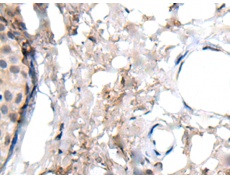

IHC positive control:

Human liver cancer and human lung cancer

IHC Recommend dilution:

25-100